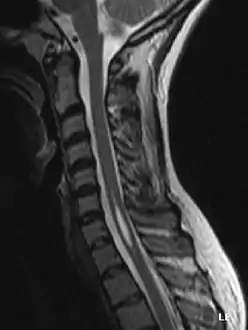

![]() صورة بالرنين المغناطيسي لكيس (أو syrinx) مجهول السبب موجود بين الفقرتين الرقبيتين السادسة والسابعة. لاحظ اللون الرمادي الفاتح داخل النخاع الشوكي في وسط الصورة. صورة بالرنين المغناطيسي لكيس (أو syrinx) مجهول السبب موجود بين الفقرتين الرقبيتين السادسة والسابعة. لاحظ اللون الرمادي الفاتح داخل النخاع الشوكي في وسط الصورة. | |